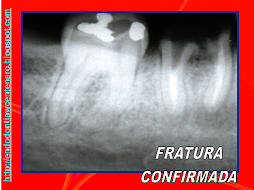

ENDO-OCLUSÃO

A ENDODONTIA PODE FRACASSAR SE A OCLUSÃO TIVER AJUSTADA

PELO DESGASTE APRESENTADO DA PARA IMAGINAR O QUE VAI ACONTECER!!!

SERÁ?

DOR!!!!!!!!!!!!!!!!!

É DA ENDO?

TINHA QUE DAR NISTO!!!!

E AGORA?